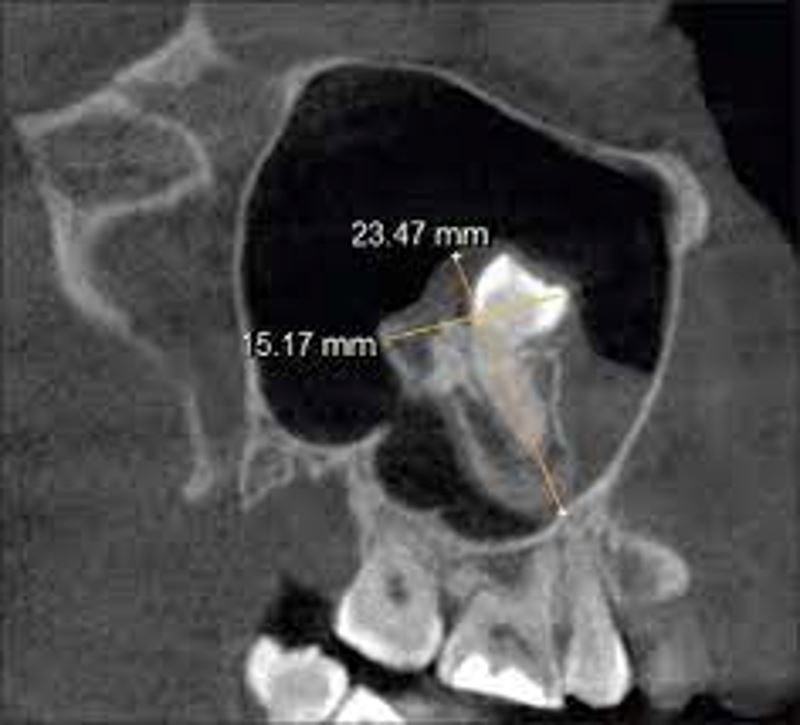

A CT scan revealed the startling diagnosis: a tooth growing inside the nasal cavity.

Medically, the man had an “inverted ectopic tooth” which developed in his nose. Ectopic teeth are when teeth grow in the wrong places which are extremely rare.

But luckily, oral and otolaryngologic surgery allowed doctors to remove the tooth. Three months following the surgery, the patient’s nasal blockage had disappeared which indicated that there were no postoperative complications.